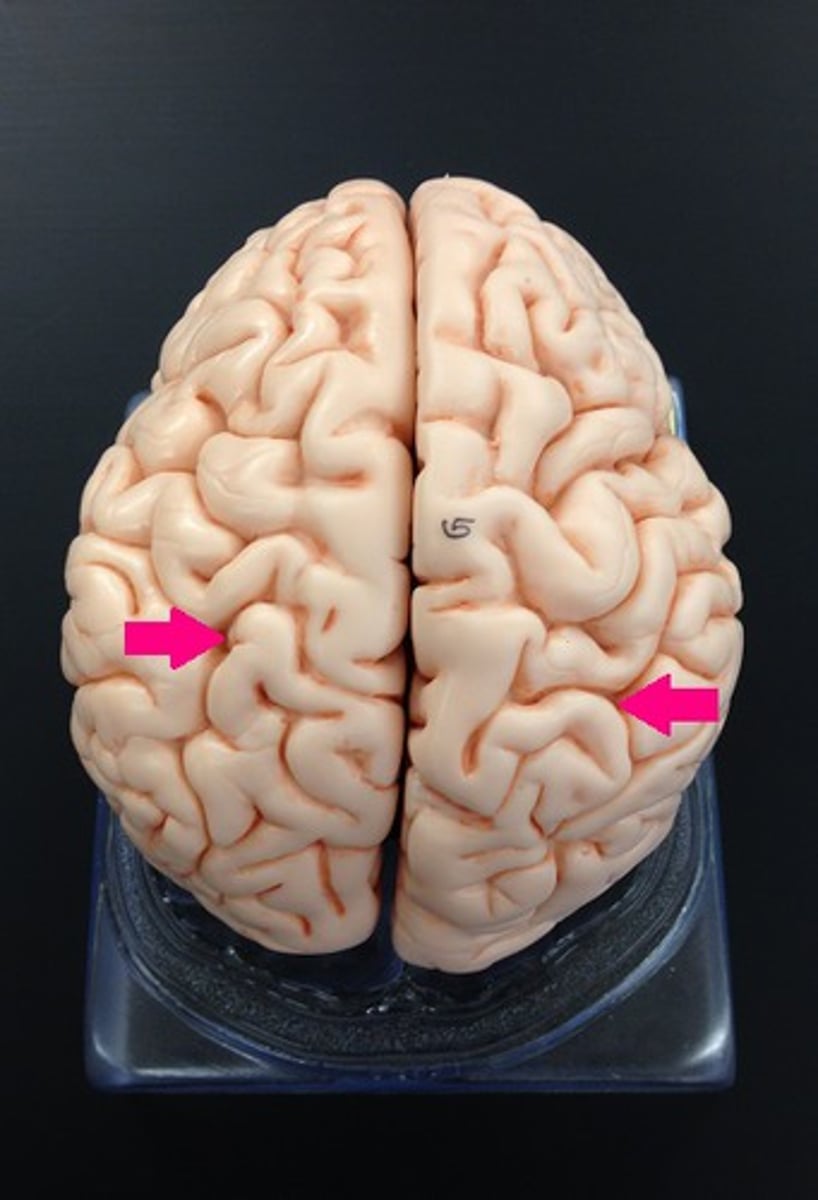

Superior Dorsal View of brain

Gyri

Sulci

Longitudinal Cerebral Fissure

Frontal Lobe

Parietal Lobe

Occipital Lobe

Central Sulcus

Lateral Sulcus